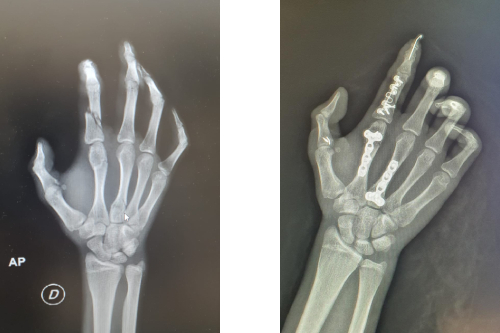

Fractura de muñeca y mano

Fractura de metacarpianos.